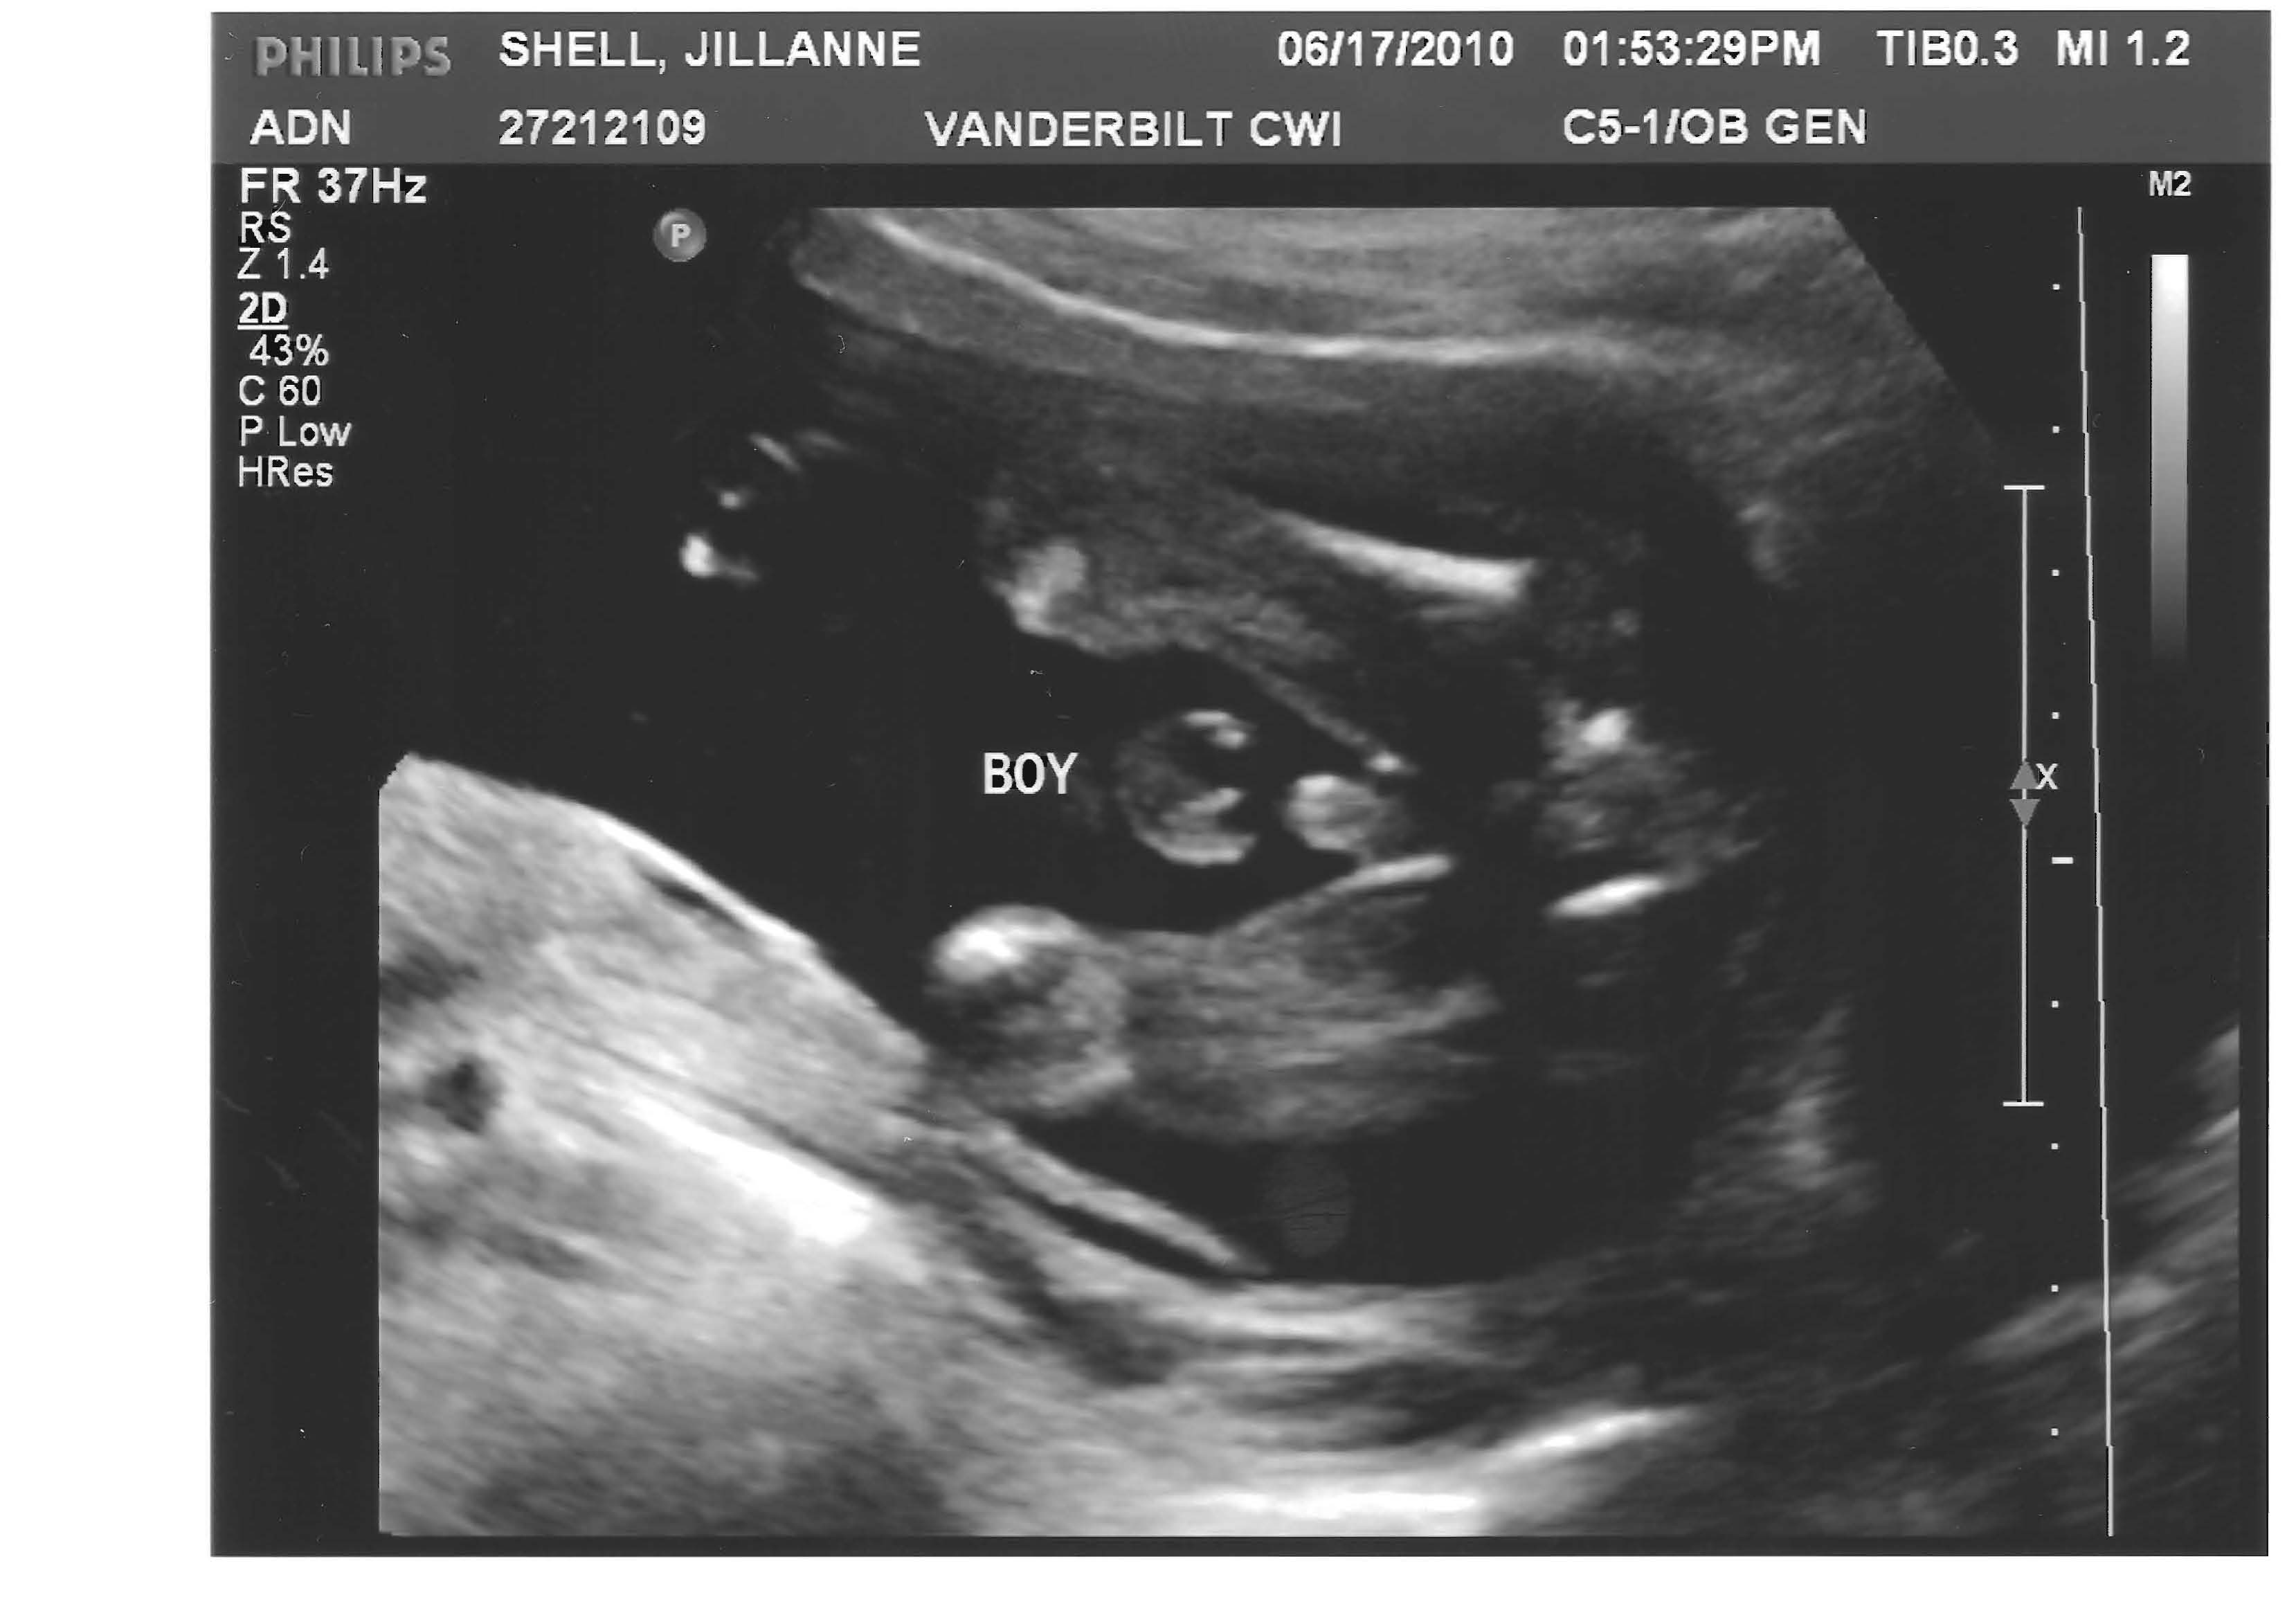

This is an “under the scrotum” shot.